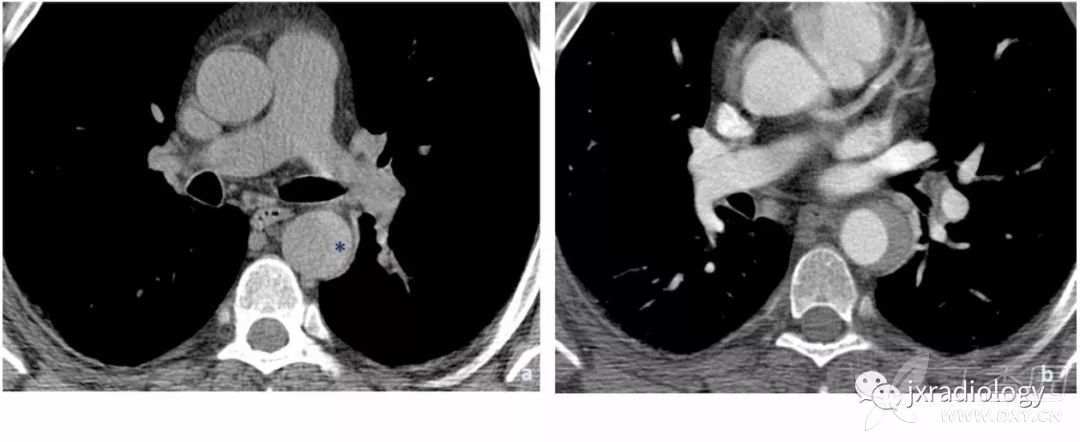

Stanford A型主动脉夹层患者出现急性心包积液时提示高死亡率,与心包填塞有关( 图16 )。

图16:平扫CT显示自发性高密度心包积液,符合心包积血(a图星号)。双侧胸腔积液可见。增强后示Stanford A型主动脉夹层,并出现假腔的局部血栓形成(b图箭头)。